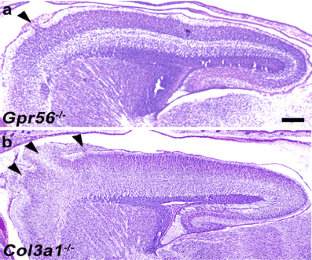

Fig. 1

Fig. 2

Fig. 3

Fig. 4

Fig. 5